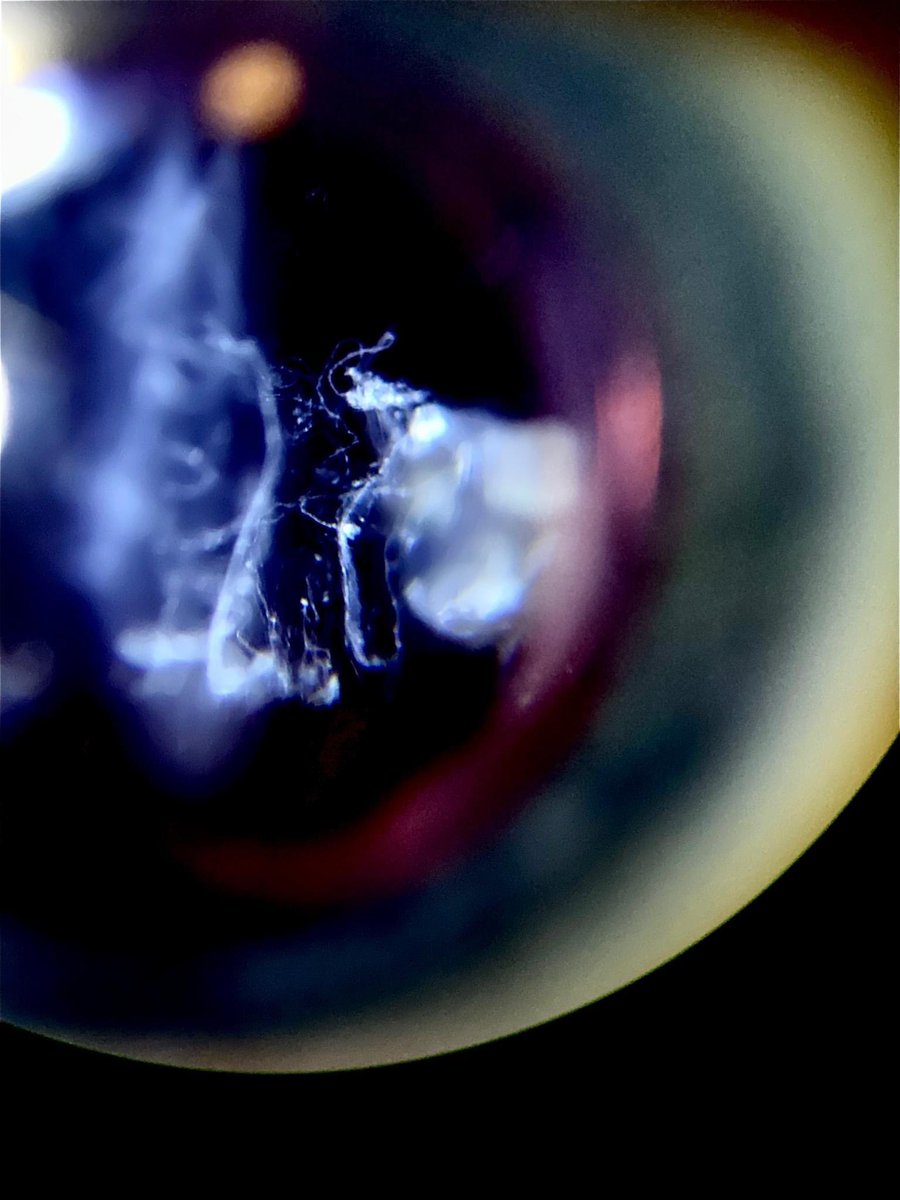

Incredible view of vitreous floaters. Although they can look like art when viewing them, they can significantly reduce quality of vision and negatively effect quality of life. Whether laser or surgery, ignoring them is not always the best option 🙂. #floaters #vitreous

Incredible view of vitreous floaters. Although they can look like art when viewing them, they can significantly reduce quality of vision and negatively effect quality of life. Whether laser or surgery, ignoring them is not always the best option 🙂.

#floaters #vitreous